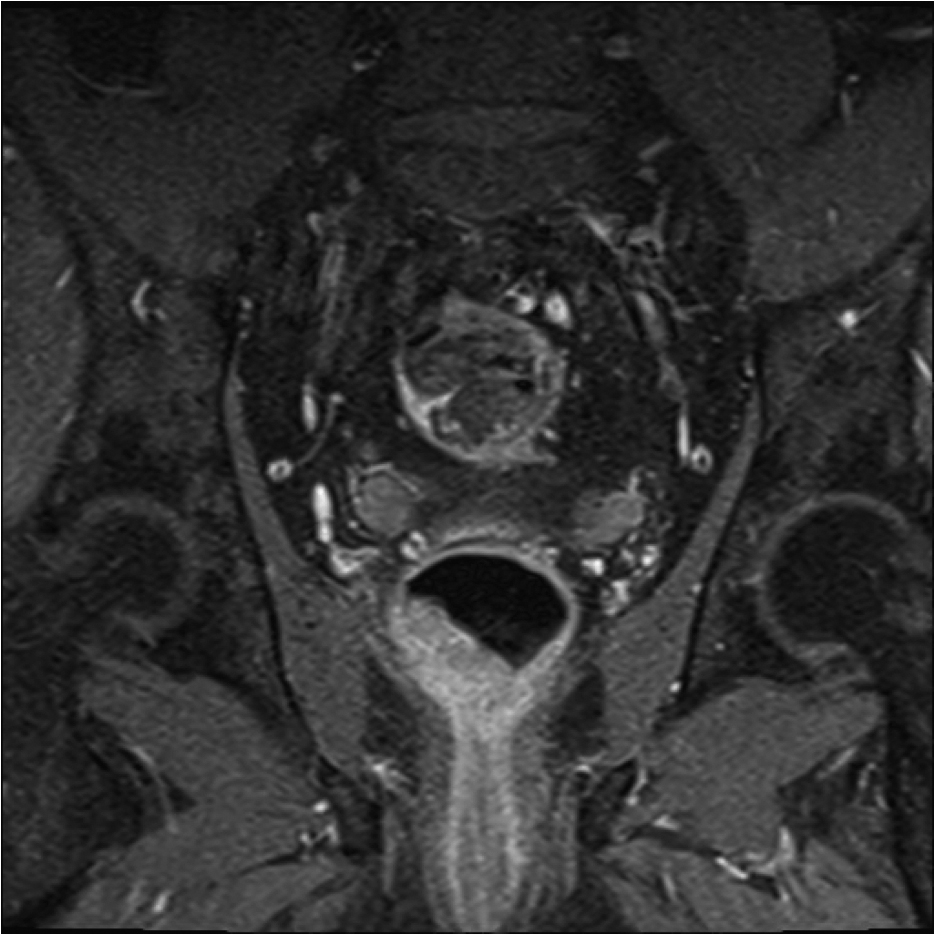

Fig1. Pacient cu neoplasm rectal stadiul IIIC (T3; N2; M0) confirmat bioptic, adenocarcinom mixt G2

a-d imagini T2 ponderate în plan sagital, oblic axial și oblic coronal – masă tisulară dezvoltată superior de joncțiunea anorectală, lateral dreapta, cu minimă extensie la nivelul grăsimii mezorectale și limfoganglioni mezorectali cu diametru de până la 10 mm;

e,f) restricție de difuzie la nivelul tumorii rectale și a doi ganglioni mezorectali

g,h,i) priză de contrast moderată la nivelul tumorii rectale și al ganglionilor mezorectali

j) reconstrucții curbe în planul adevărat al rectului, cu evidențiere mai bună a fasciei mezorectale